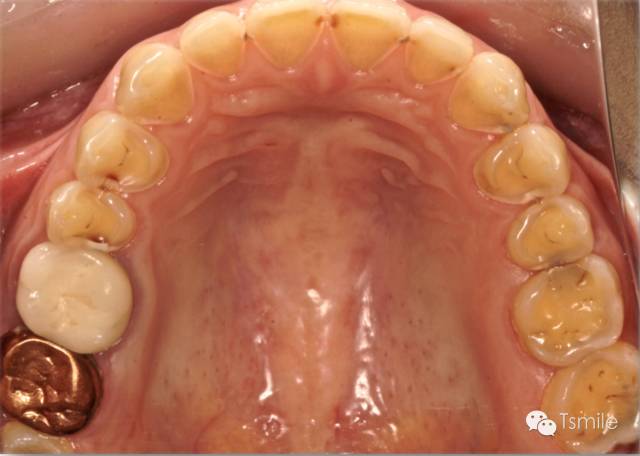

圖2: 長期飲用碳酸飲料導(dǎo)致的酸蝕癥

對(duì)牙齒酸蝕脫礦的酸來源于患者身體以外,包括飲料、食物、水果、藥物、工作環(huán)境等。碳酸類飲料如可樂,其PH值約為2.7;果汁中檸檬汁的PH值約為1.8-2.4。酸性的飲料、水果、食物等長時(shí)間、高頻度地接觸牙齒表面,導(dǎo)致牙齒表面硬組織酸蝕脫礦,造成牙齒表面硬組織的重度缺損。

磨耗發(fā)生的部位(location)物理性的磨耗由于是上下頜牙列相對(duì)的牙齒之間的機(jī)械摩擦而導(dǎo)致,因此物理性的磨耗主要發(fā)生在牙齒的咬合面。而酸蝕癥導(dǎo)致的牙列重度磨耗不一定在牙齒的咬合面,可以發(fā)生于牙齒的唇頰面或者舌顎面。

物理性的磨耗形成的磨耗面邊緣尖銳、表面光滑閃亮。而酸蝕癥導(dǎo)致的磨耗面邊緣圓鈍,多呈杯狀凹陷。

物理性的磨耗上下頜相對(duì)牙齒牙面的磨耗量基本一致。而酸蝕癥導(dǎo)致的牙列重度磨耗上下頜相對(duì)牙齒牙面的磨耗量可以完全不同,甚至一側(cè)有嚴(yán)重的磨耗而對(duì)側(cè)完全沒有磨耗。

物理性的磨耗所導(dǎo)致的牙列重度磨耗,其上下頜相對(duì)牙齒的磨耗面之間一定有咬合接觸。而化學(xué)性酸蝕癥所導(dǎo)致的牙列重度磨耗,其上下頜相對(duì)牙齒的磨耗面之間可能完全沒有咬合接觸。